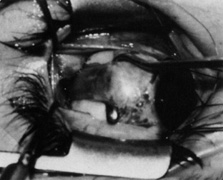

Step 3. Although traction is applied on the superior rectus with the large muscle hook to depress the globe, a Stevens hook held in the other hand is used to expose the superior rectus insertion by reflecting the intermuscular septum, Tenon's capsule, and conjunctiva over the toe of the large hook as shown in Figures 11A (before reflection) and 11B (after reflection).

Fig. 11. A. Traction on the superior rectus muscle with the large muscle hook is applied to depress the globe. B. A Stevens hook held in the other hand is used to expose the superior rectus insertion by reflecting the intermuscular septum, Tenon's capsule, and conjunctiva over the toe of the hook. (Del Monte MA, Archer SM: Atlas of Pediatric Ophthalmology and Strabismus Surgery. New York: Churchill Livingstone, 1993)